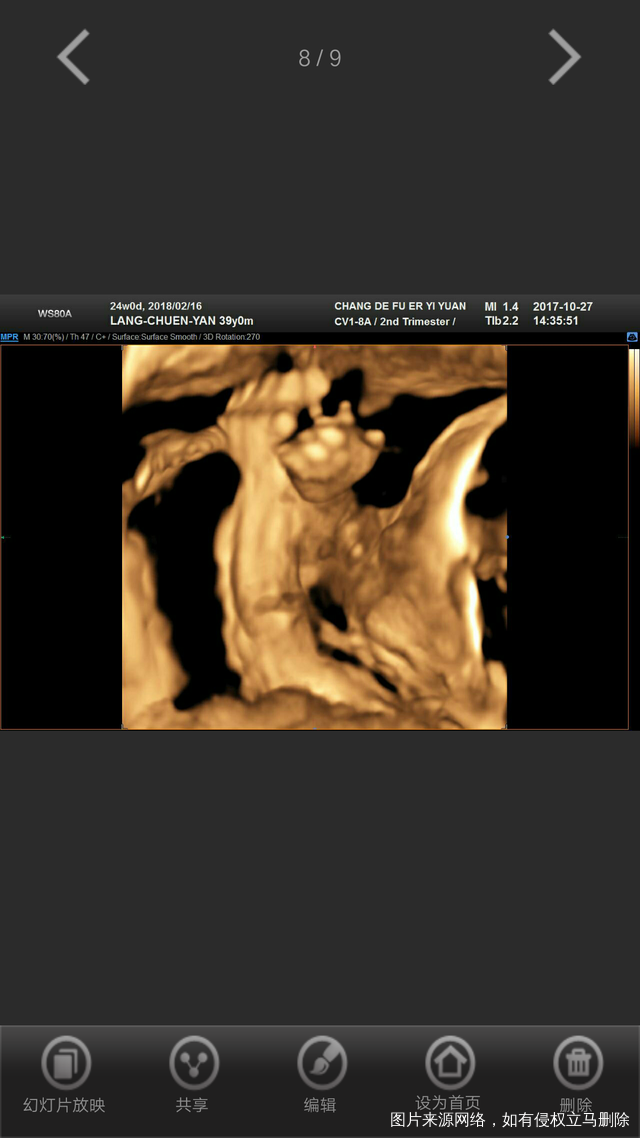

宝贝儿呀!今天正38周了,我们相见的日子更近了